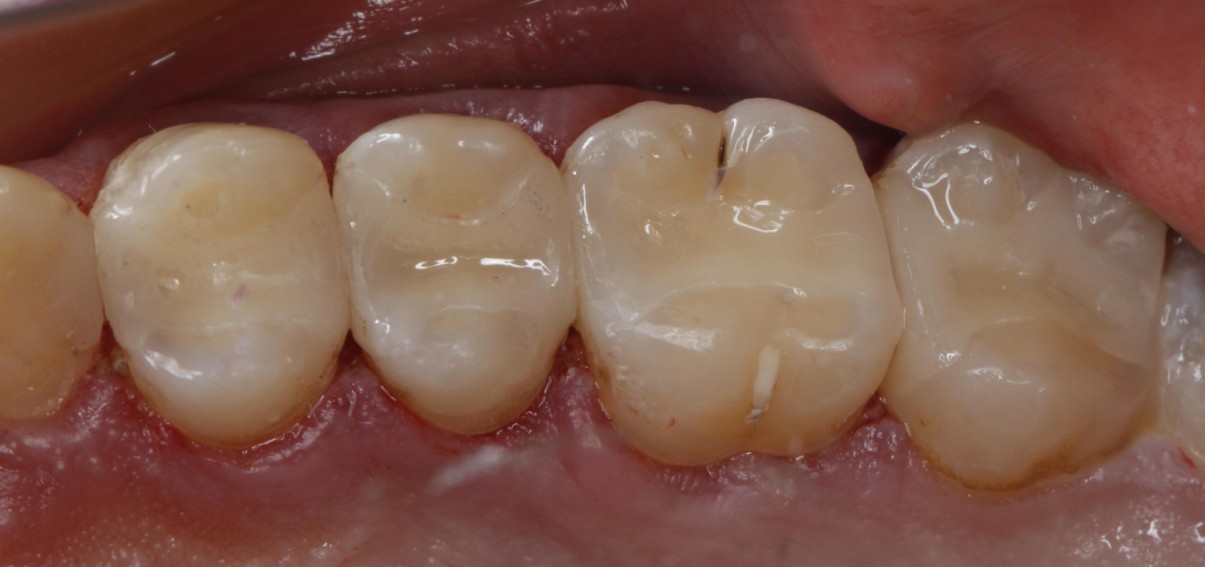

门诊经常遇到常年把碳酸饮料当水喝的患者,严重损伤了牙齿的健康,检查发现牙齿脱矿.龋坏特别严重,特别是邻面龋坏,治疗也非常麻烦,很多情况下,简单的补牙都解决不了长久性问题,想要经久耐用,可以选择嵌体,高嵌体,全瓷牙冠修复,更重要是杜绝不良嗜好;有图有真相!我们采用德国西诺德瓷睿刻即刻修复系统,等待1小时,完成当日修复。